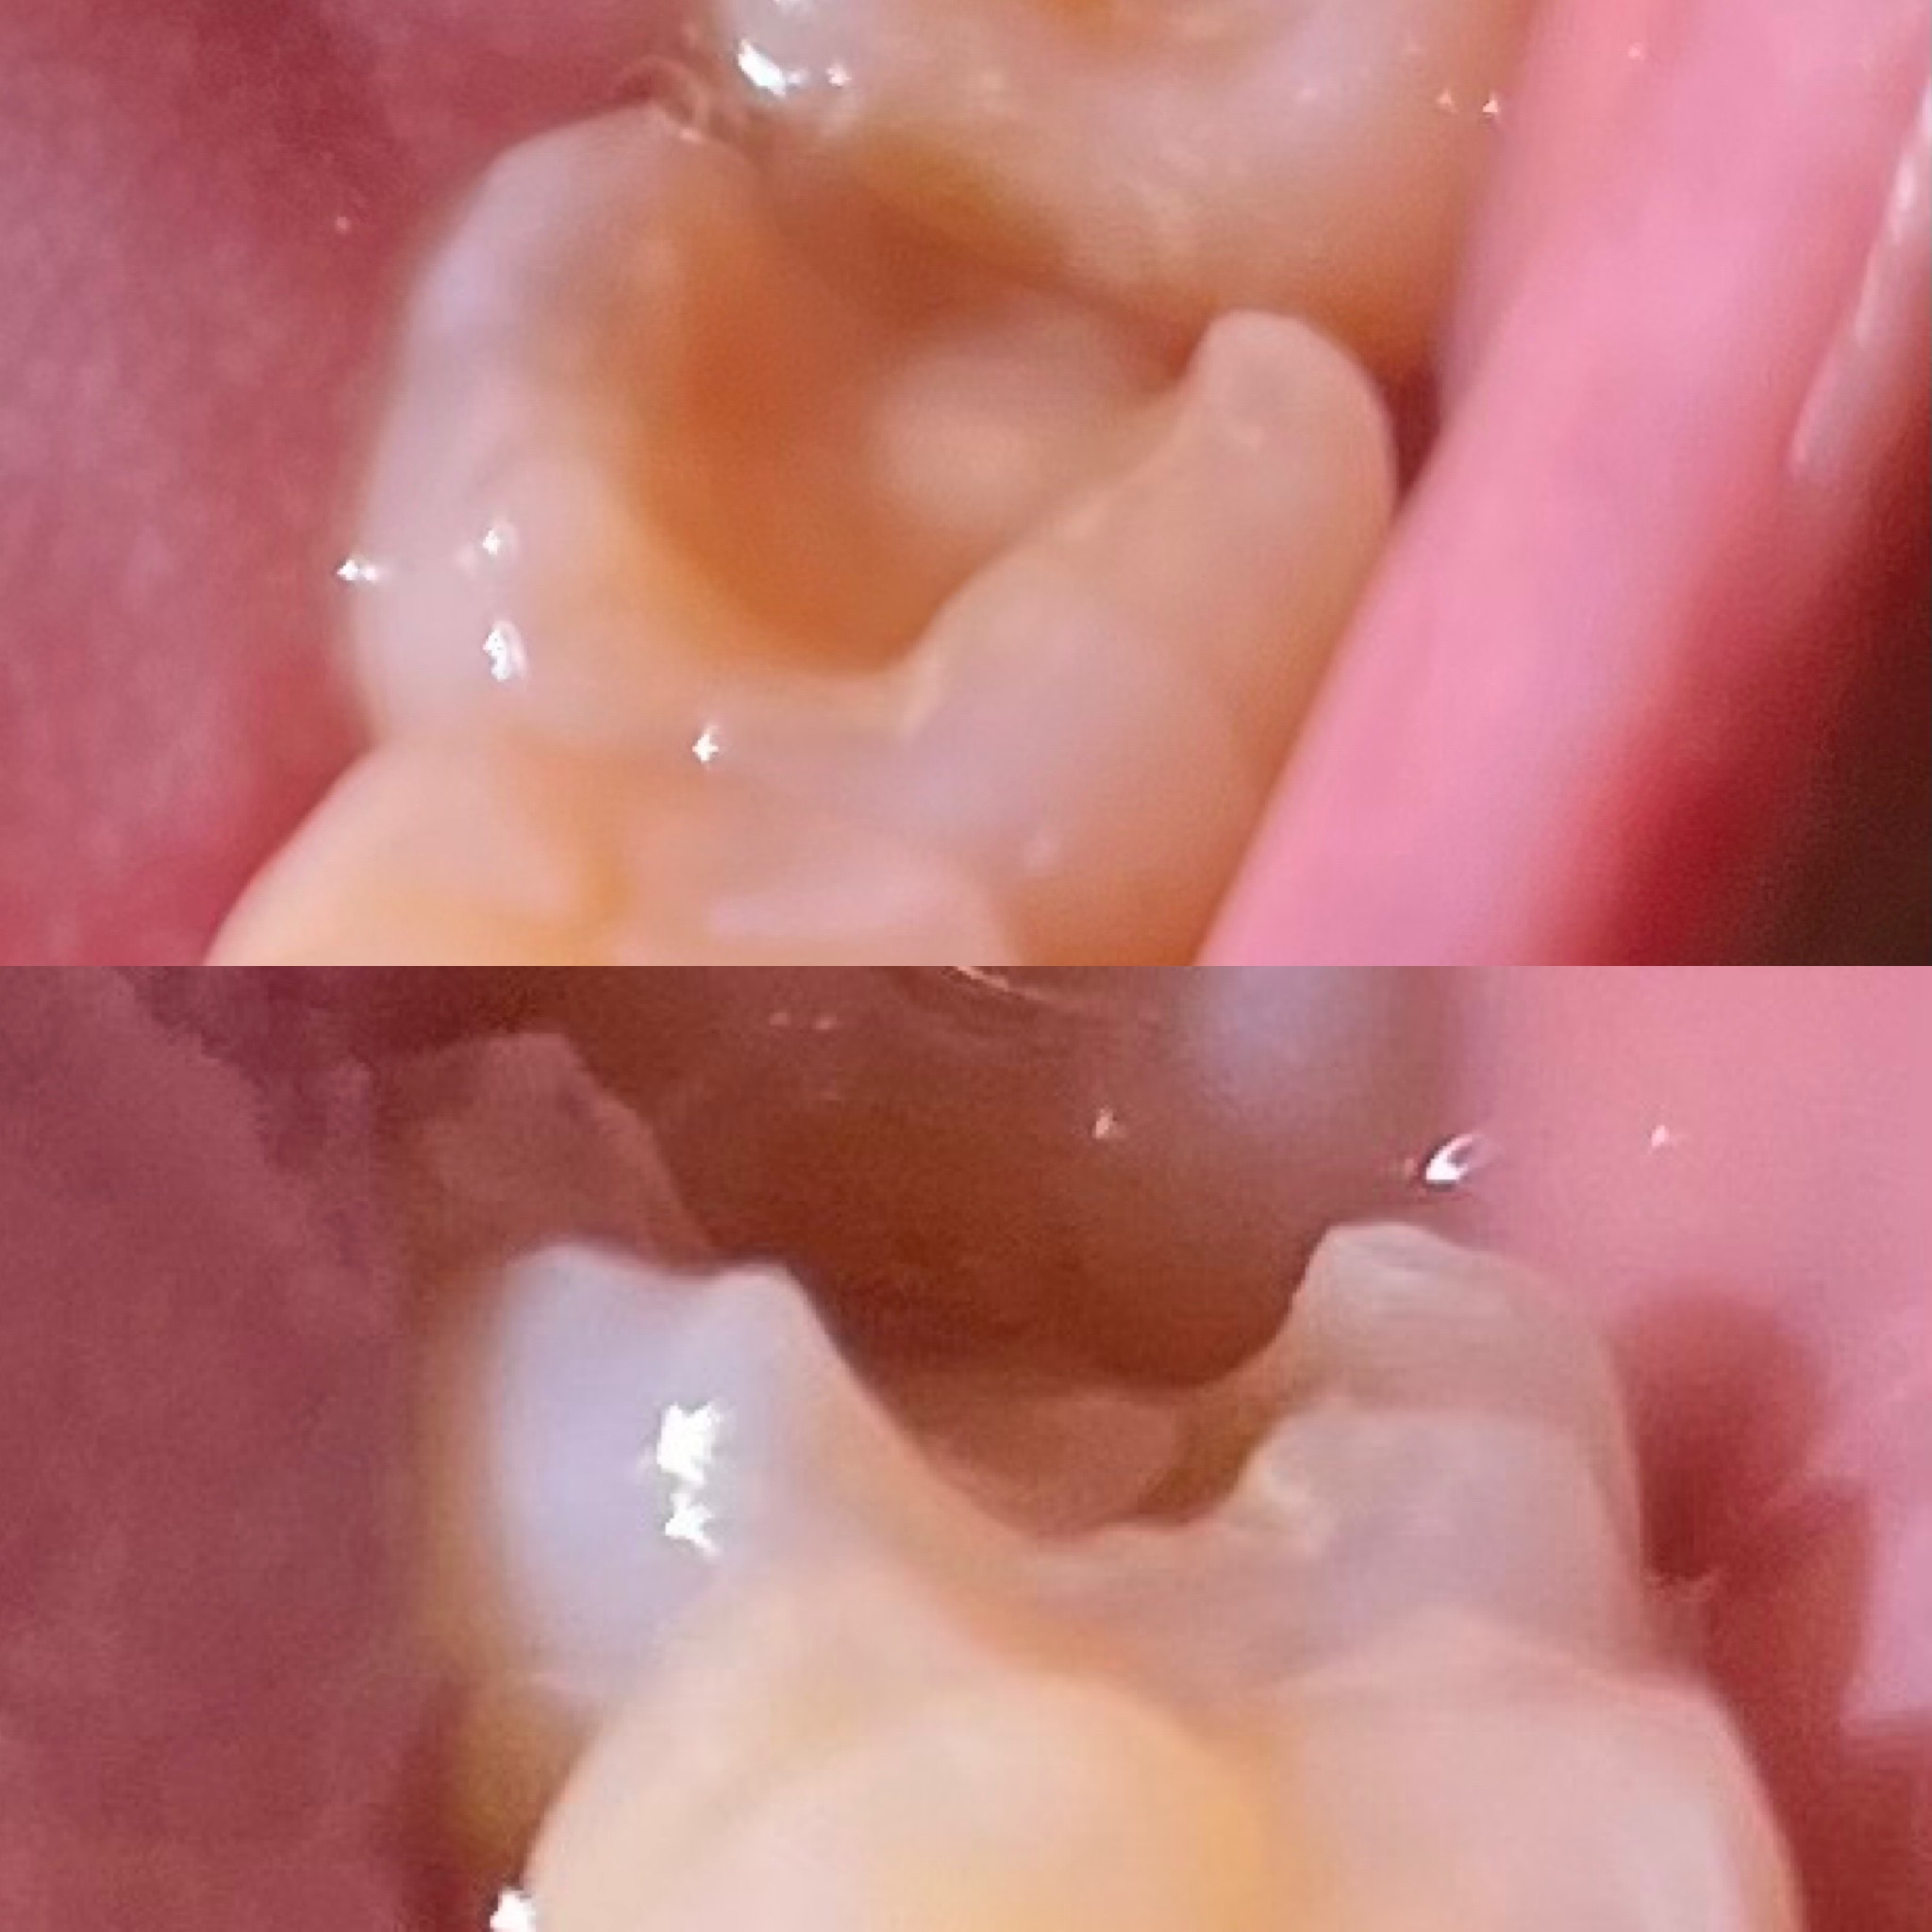

画像を見ていただきたいんですが、これが仮詰め後です。

取れたのではなく、ちゃんと詰めた後です。

薬を詰めて、光る機械?みたいなもので固められました。

舌で触った感じも歯の角が分かるし、チクチク、軽いズキズキもあります。

歯は左下奥から2番目です。

こんなに仮詰めが薄くて歯が欠けたりしないか心配です。

欠ける事と仮ヅメは関係ないかもしれませんが、量的には少ないか取れてしまった可能性があると思います。